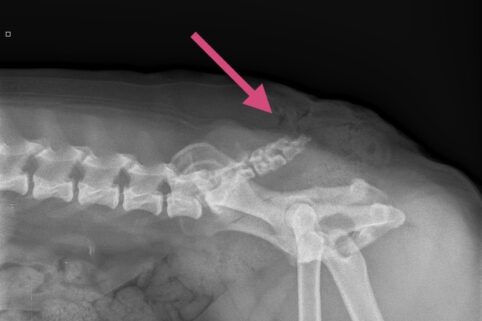

Før operationen tages et røntgenbillede af bagparten, så halehvirvlernes placering kan vurderes.

Der lægges et ovalt snit rundt omkring halens tilhæftning på rumpen. Ud fra røntgenbillederne vurderes halehvirvlernes udformning og ud fra dette besluttes, hvor snittet skal lægges. Det er stort set aldrig muligt at bevare noget af halen.

Huden sys sammen, og der tages et nyt røntgenbillede af halen.